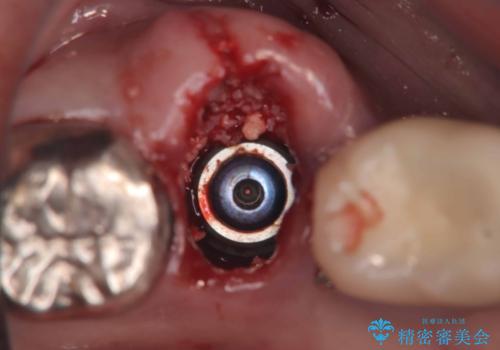

歯の保存は困難と診断しインプラントで治療を行いました。1Dayインプラントの適応だったので、抜歯した当日にインプラントを埋入しました。

1Dayインプラントは低侵襲なので痛みもほとんどありません。従来のインプラント治療だと1年弱かかるのが、3ヵ月で治療を終える事が出来ました。

1Dayインプラントとは抜歯と同時にインプラントを埋入する治療です。

従来のインプラント治療よりも低侵襲かつ短期間で治療を終える事が出来ます。